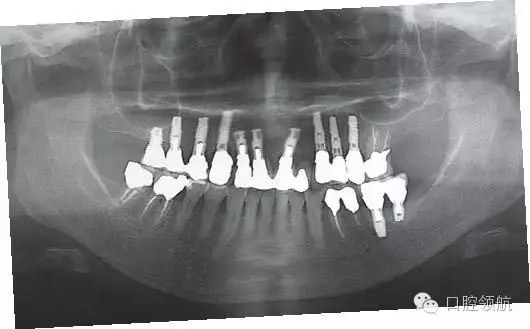

(左上第4顆牙)種植體周圍骨組織吸收的原因是種植體植入的位點(diǎn)偏頰側(cè),植入的方向也向頰側(cè)傾斜,考慮到以上原因,按照正確的種植體位置和方向植入后(圖3),上部修復(fù)體是使用氧化鈷為基底的全瓷冠,采用螺絲直接固位到種植體上的構(gòu)造(圖4~圖6)。

圖6 修復(fù)戴入后的全景X線片。

另外,為了避免露出固位的螺絲孔,也可以使用氧化鈷基臺(tái)粘接固位方式固定全瓷冠的方法。